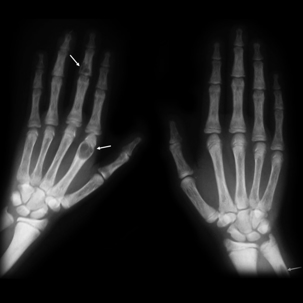

X-ray broken hands

Ouch!

Broken bones never lead to a humerus time, but unfortunately, fractures are fairly common—especially when it comes two on-the-job injuries. As a workers’ compensation lawyer serving Atlanta, a lot of cases come through my door involving fractures. Today, I want to go over some of the details about broken bones: